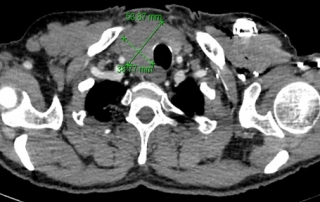

Scanner comparé au scanner avant traitement, la cible axillaire droite taille 18 x 9 mm

vs 32 x 31 mm soit une régression de 84% sur cette cible.